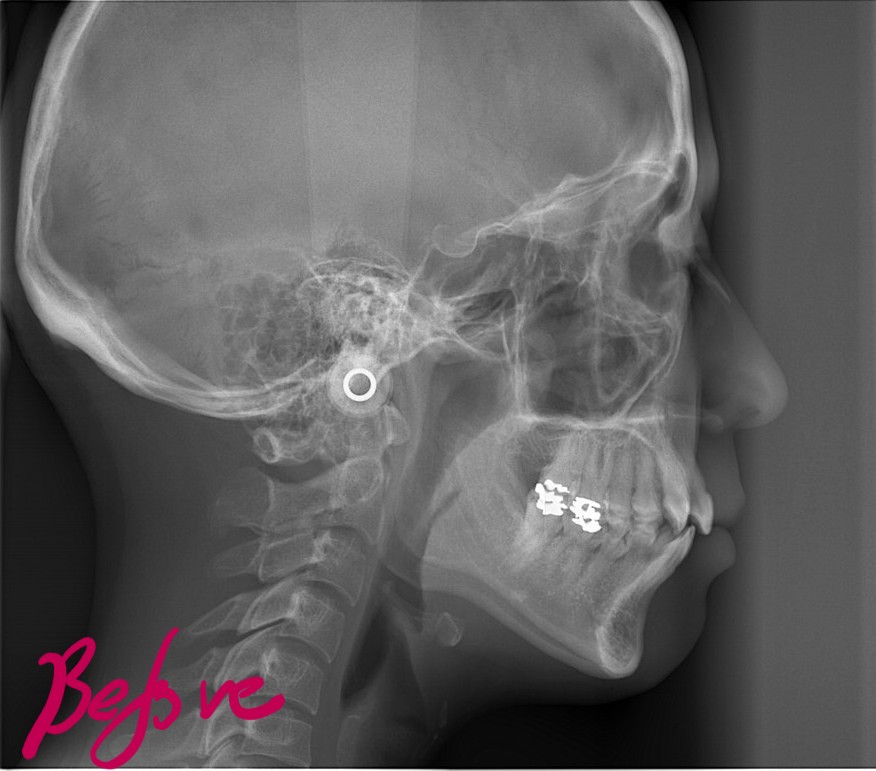

レントゲン写真で確認すると、

この患者さんの場合、

レントゲン写真でも矯正治療前後を比較してみましょう